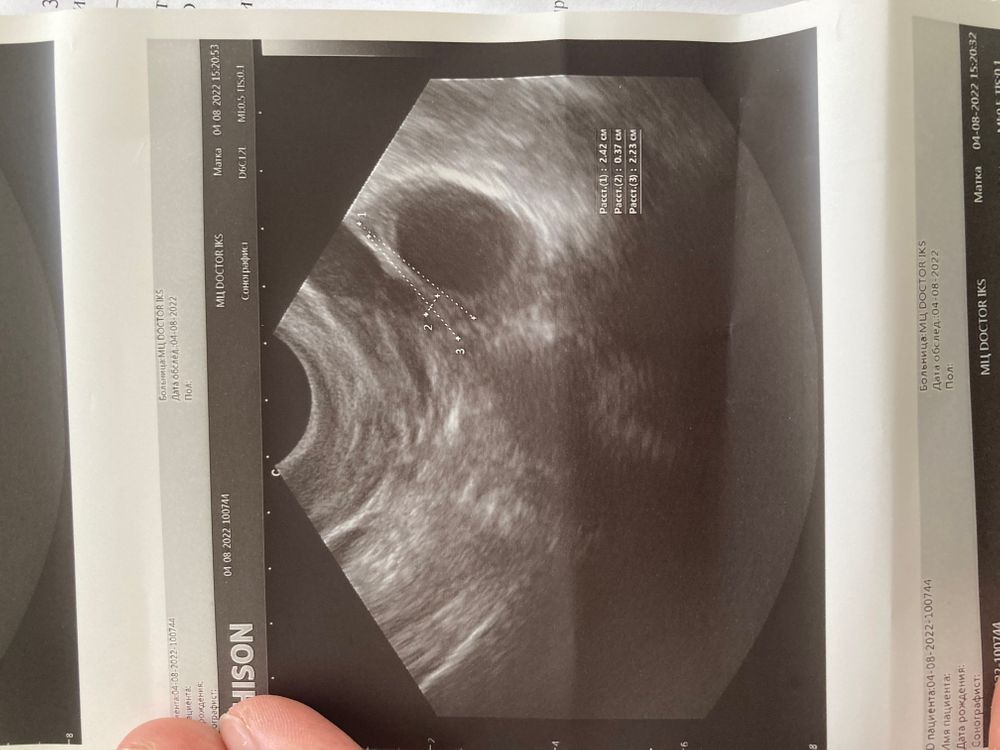

Что это?узи фолликулометрия

Доминантный фолликул ?Желтое. Тело?или Киста ?есть малое количество жидкости позади матки еще(незначительное)

Это фолликул. Какой размер намерили? Это точно не Желтое тело тк желтое тело с перегородками

Ну пока просто нелопнувший фолликул , будет размером ближе к 30 и без перспективы к овуляции то будет киста , на жт не похоже